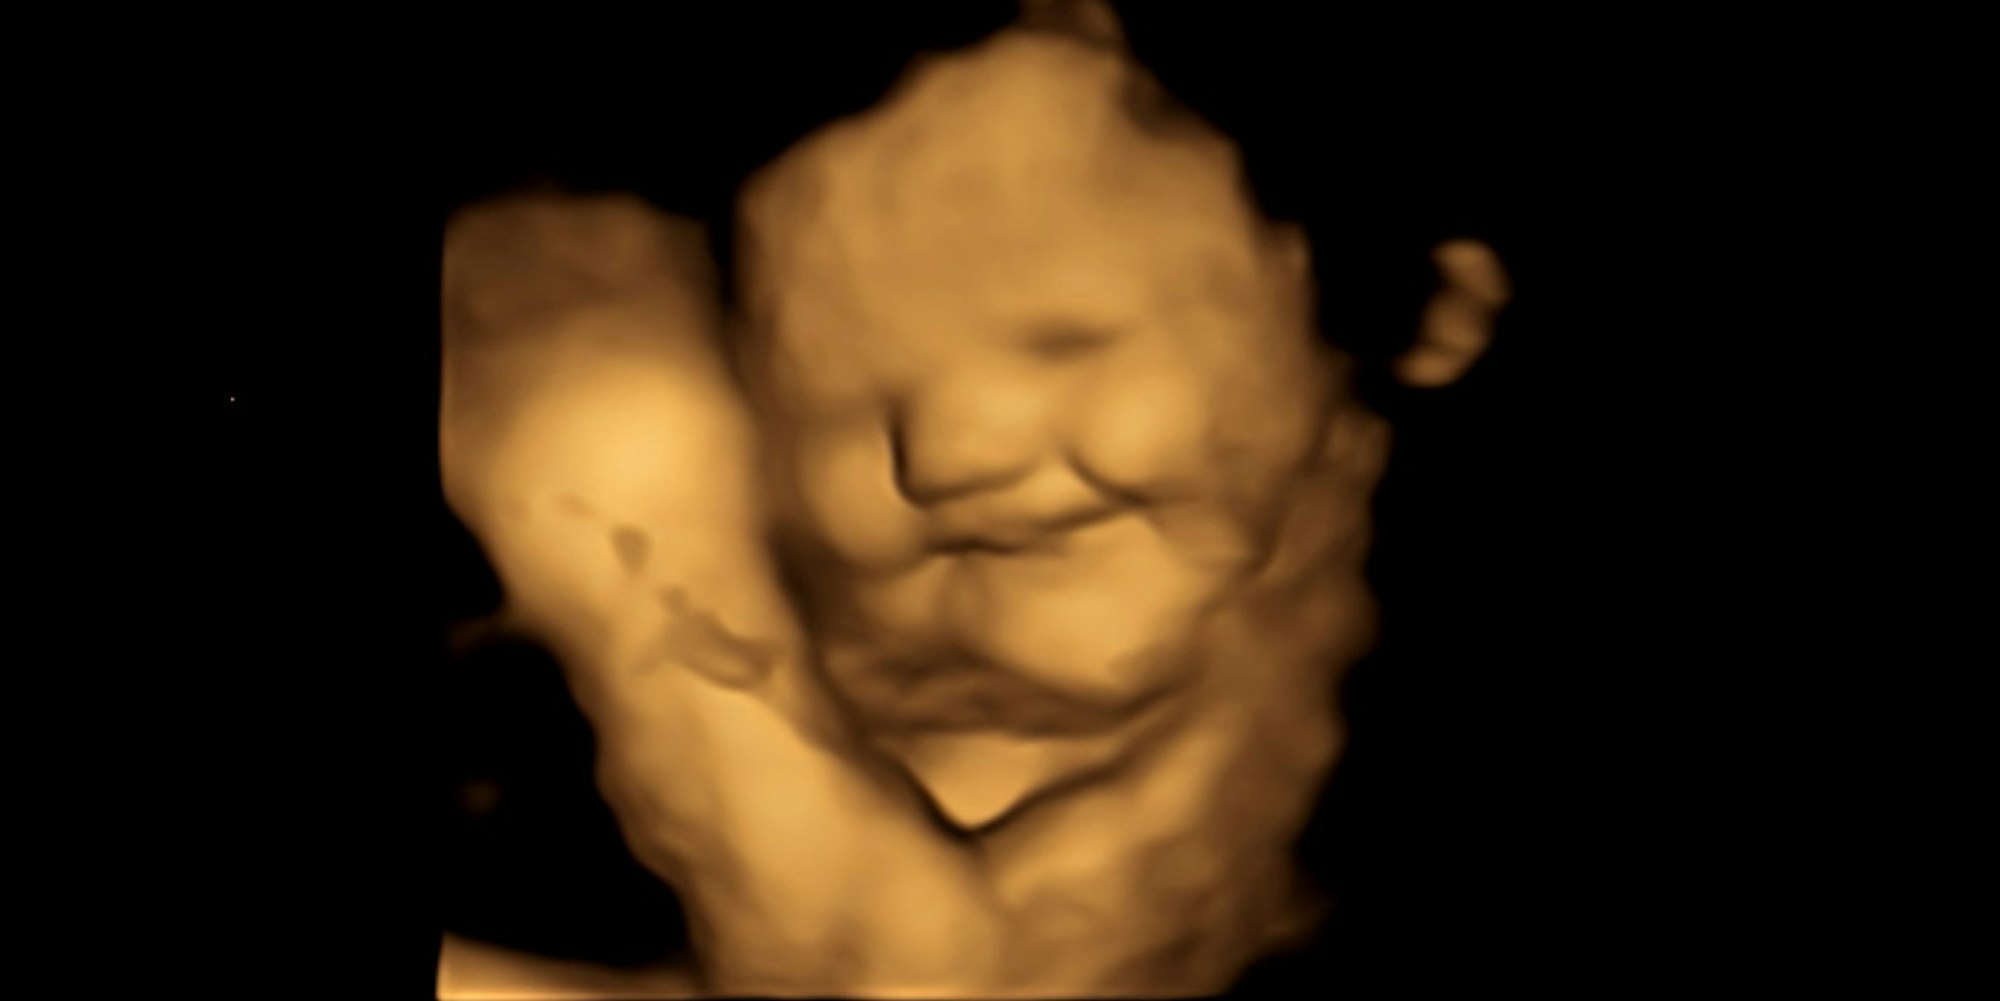

Fötus mit Lachgesicht-Reaktion (4D-Scan-Bild).

Copyright: dpa/FETAP Study/Fetal and Neonatal Research Lab/Durham University

Durham – Bereits im Mutterleib reagieren Babys einer Studie zufolge positiv oder negativ auf manche Lebensmittel. So hätten Föten ein eher „lächelndes Gesicht“ gezeigt, nachdem ihre Mütter Karotten gegessen hätten, berichten Wissenschaftler der nordostenglischen Universität Durham in der Fachzeitschrift „Psychological Science“. Nach dem Genuss von Kohlaromen hingegen hätten die Föten ein eher „weinendes Gesicht“ gemacht.